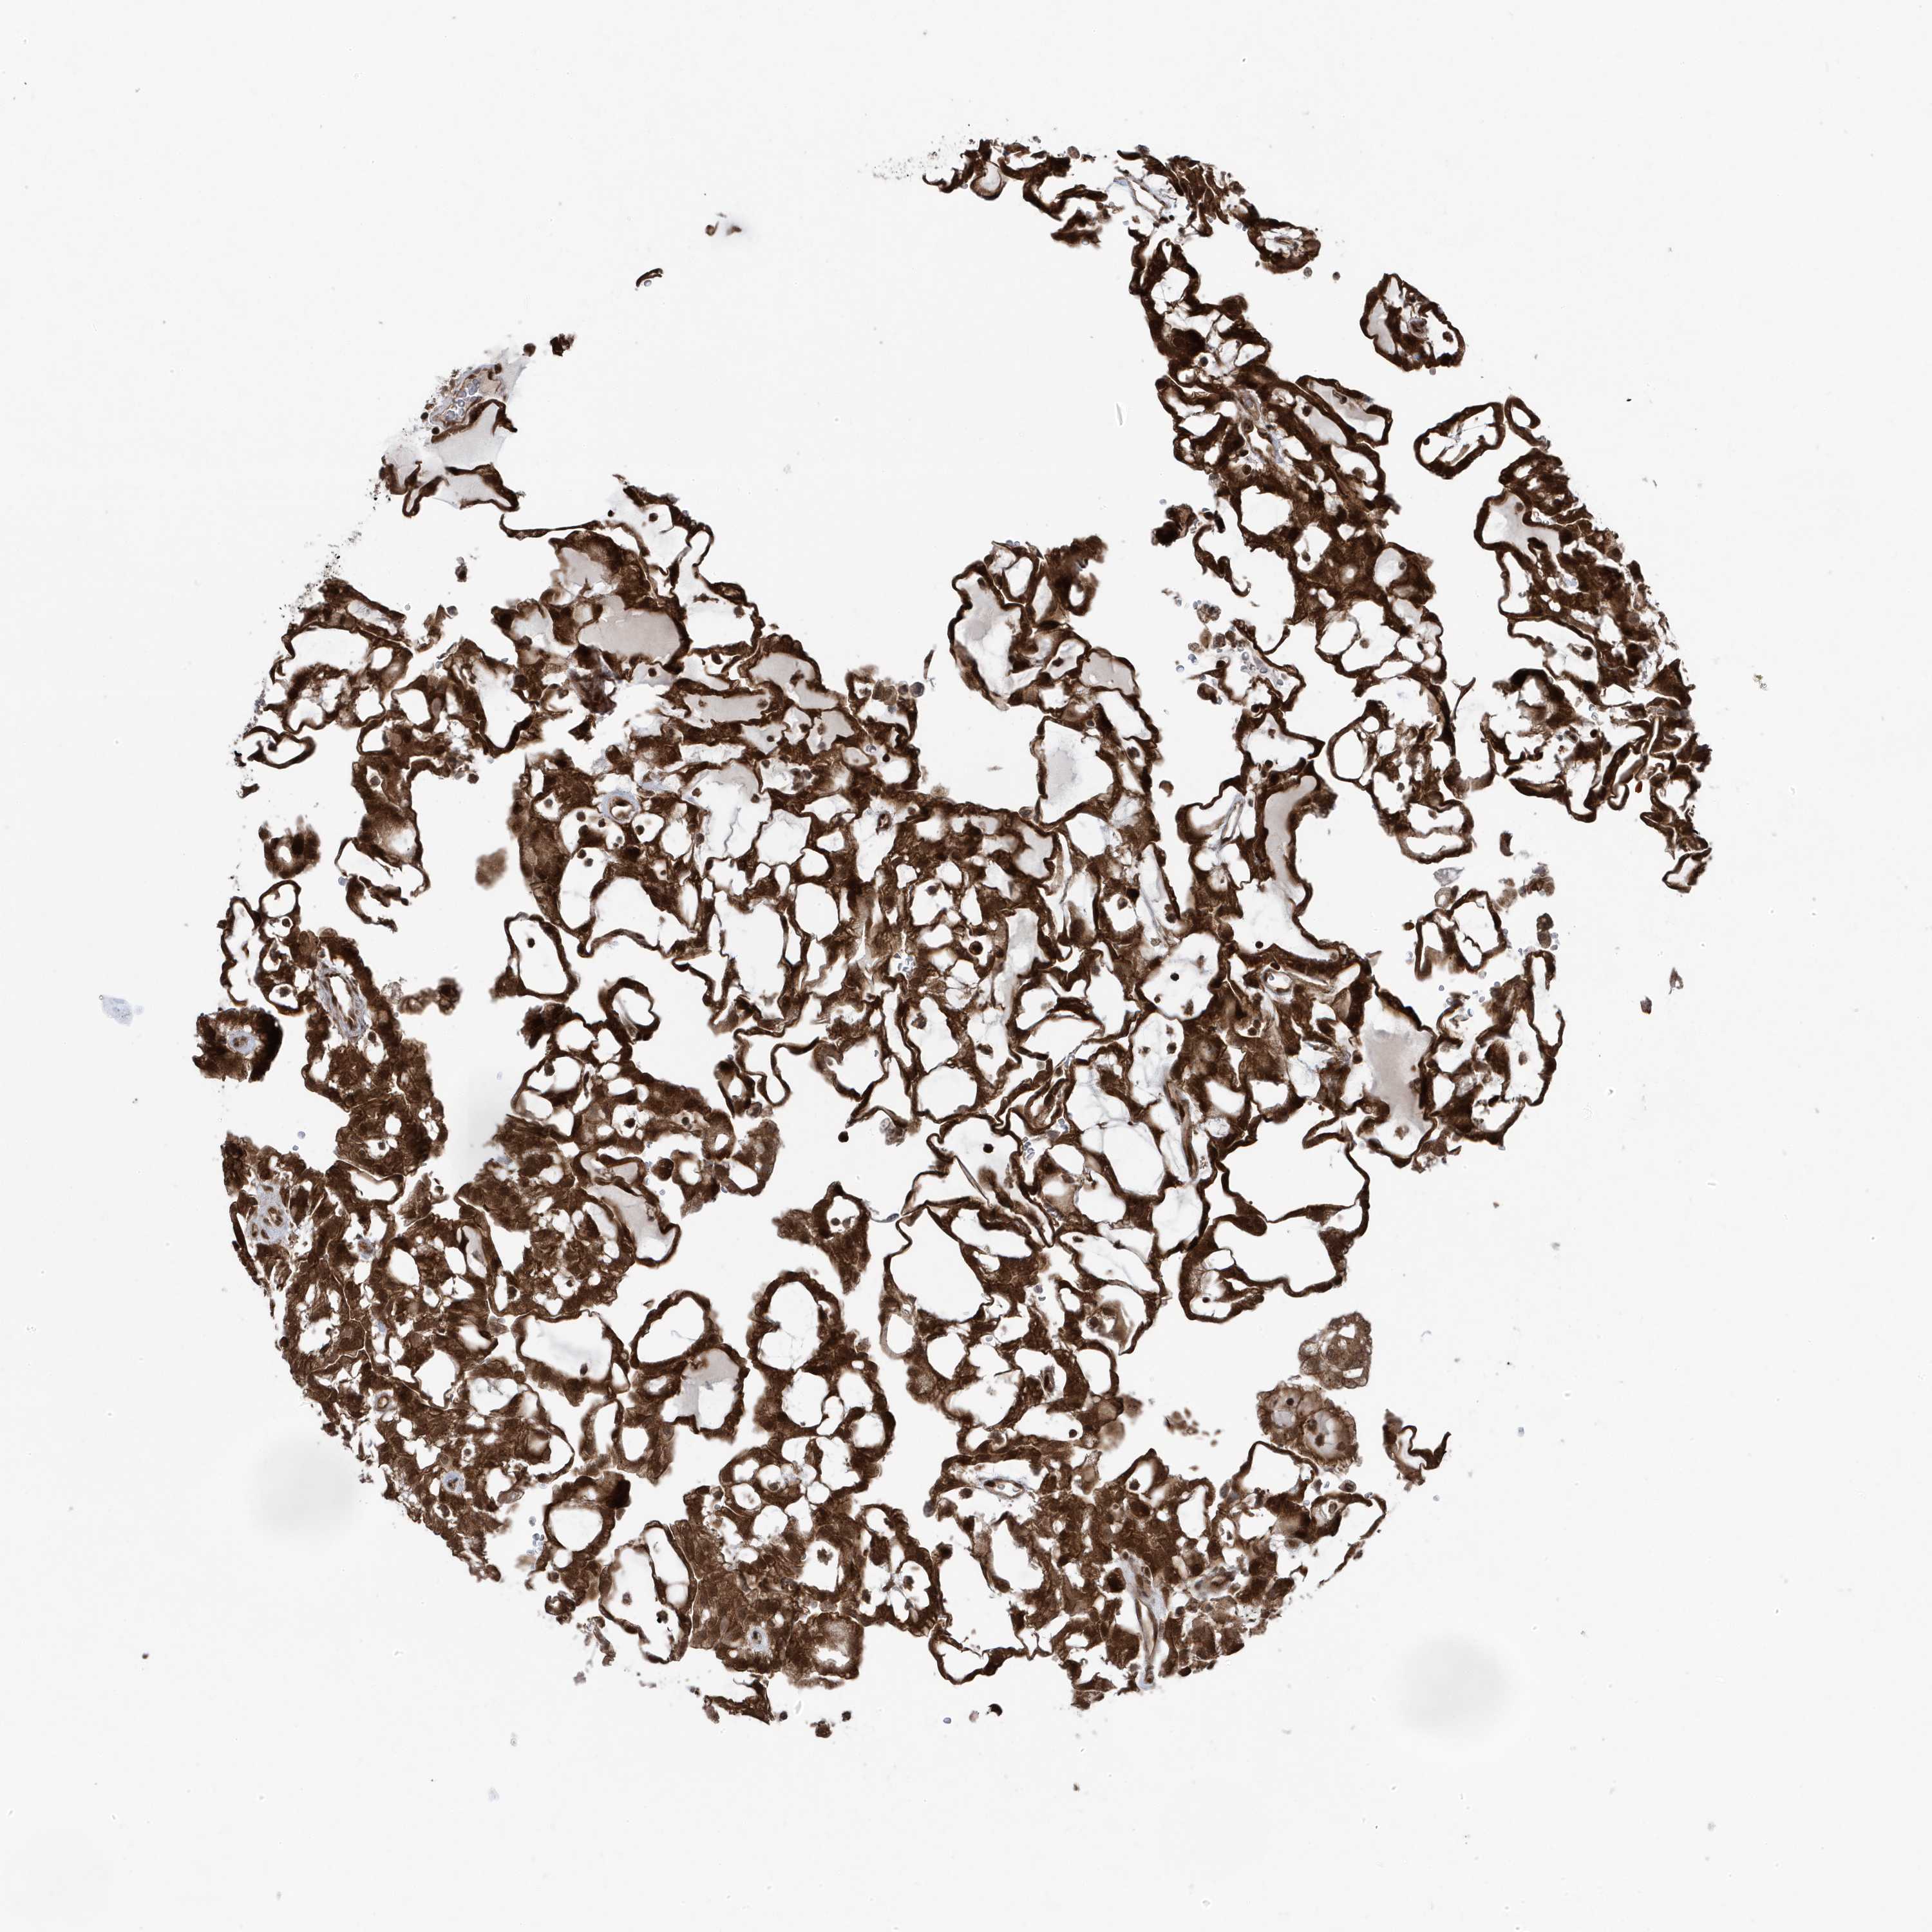

KIDNEY RENAL PAPILLARY CELL CARCINOMA (TCGA) - Interactive survival scatter ploti

The Survival Scatter plot shows the clinical status (i.e. dead or alive) for all individuals in the patient cohort, based on the same data that underlies the corresponding Kaplan-Meier plots. Patients that are alive at last time for follow-up are shown in blue and patients who have died during the study are shown in red.

The x-axis shows the expression levels (FPKM) of the investigated gene in the tumor tissue at the time of diagnosis. The y-axis shows the follow-up time after diagnosis (years). Both axes are complimented with kernel density curves demonstrating the data density over the axes. The top density plot shows the expression levels (FPKM) distribution among dead (red) and alive patients (blue). The right density plot shows the data density of the survived years of dead patients with high and low expression levels respectively, stratified using the cutoff indicated by the vertical dashed line through the Survival Scatter plot. This cutoff is automatically defined based on the FPKM cutoff that minimizes the p-score. The cutoff can be changed by dragging the vertical line or by entering a cutoff value in the square labeled "Current cut-off".

Under the Survival Scatter plot the p-score landscape (black curve; left axis) is shown together with dead median separation (red curve; right axis). Dead median separation is the difference in median mRNA expression between patients who have died with high and low expression, respectively. It is calculated as follows: median FPKM expression of dead patients with high expression - median FPKM expression of dead patients with low expression. This is intended to aid the user in visually exploring custom cutoffs and the associated p-scores and dead median separation.

Individual patient data is displayed and can be filtered by clicking on one or more of the category buttons on the top of the page. Categories describing expression level and patient information include: high, low, alive, dead, female, male and tumor stages. The scale of the x-axis can be toggled between linear and log-scale by clicking on the "x log" button. Mouse-over function shows TCGA ID, patient information and mRNA expression (FPKM) for each patient.

& Survival analysisi

Kaplan-Meier plots summarize results from analysis of correlation between mRNA expression level and patient survival. Patients were divided based on level of expression into one of the two groups "low" (under cut off) or "high" (over cut off). X-axis shows time for survival (years) and y-axis shows the probability of survival, where 1.0 corresponds to 100 percent.

MAPK1IP1L is not prognostic in Kidney Renal Papillary Cell Carcinoma (TCGA)